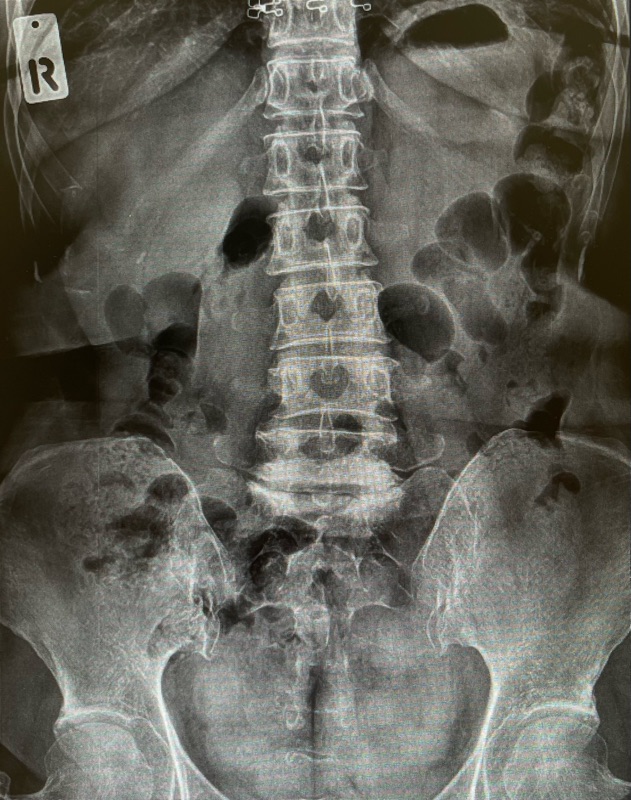

✔ 2) เอกซเรย์หลัง (X-ray)

ดูความเสื่อม การเคลื่อนของกระดูก ความผิดรูป